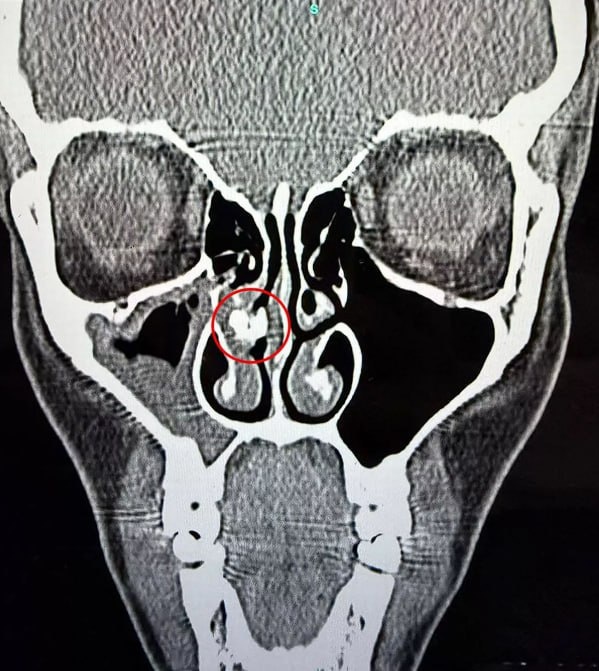

Женщина 35 лет жила с комком скотча в носу и не знала об этом. Кендела Рейбо из Великобритании испытывала трудности с дыханием столько, сколько себя помнила. Они мешали ей заниматься спортом и нормально спать. В одночасье все изменилось: проблема возникла по вине врачей в роддоме. Они вводили ей носовую трубку, а потом просто забыли удалить пластырь. Англичанка выяснила это, когда сделала КТ после синусита. Теперь в возрасте 35 лет она наконец-то может вдохнуть полной грудью. ⭕️ Подписаться | Мы в MAX | Буст

Женщина 35 лет жила с комком скотча в носу и не знала об этом.

Кендела Рейбо из Великобритании испытывала трудности с дыханием столько, сколько себя помнила. Они мешали ей заниматься спортом и нормально спать. В одночасье все изменилось: проблема возникла по вине врачей в роддоме.

Они вводили ей носовую трубку, а потом просто забыли удалить пластырь. Англичанка выяснила это, когда сделала КТ после синусита. Теперь в возрасте 35 лет она наконец-то может вдохнуть полной грудью.